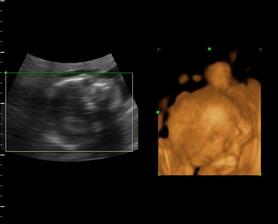

Naša Emilly

Zaciname 39tt, termin mame 23.10.09, uvidime, kedy sa malej bude chciet ist na svet a vidiet svojich rodicov. Sice sme mali neplanovane tehotenstvo, ale o to viac nas to potesilo a na malu sa nesmierne obaja tesime..je to u nas prve vnucatko, tak to bude lasky a lasky, ale tej dame aj druhemu aj tretiemu babu, uvidime, kolko nam ich zivot da. I ked mamina este studuje, urcite to zvladneme..